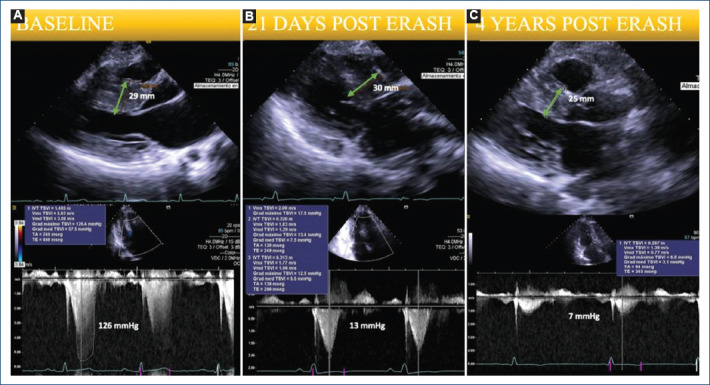

Endocardial radiofrequency ablation of septal hypertrophy: a four-year follow-up case report.